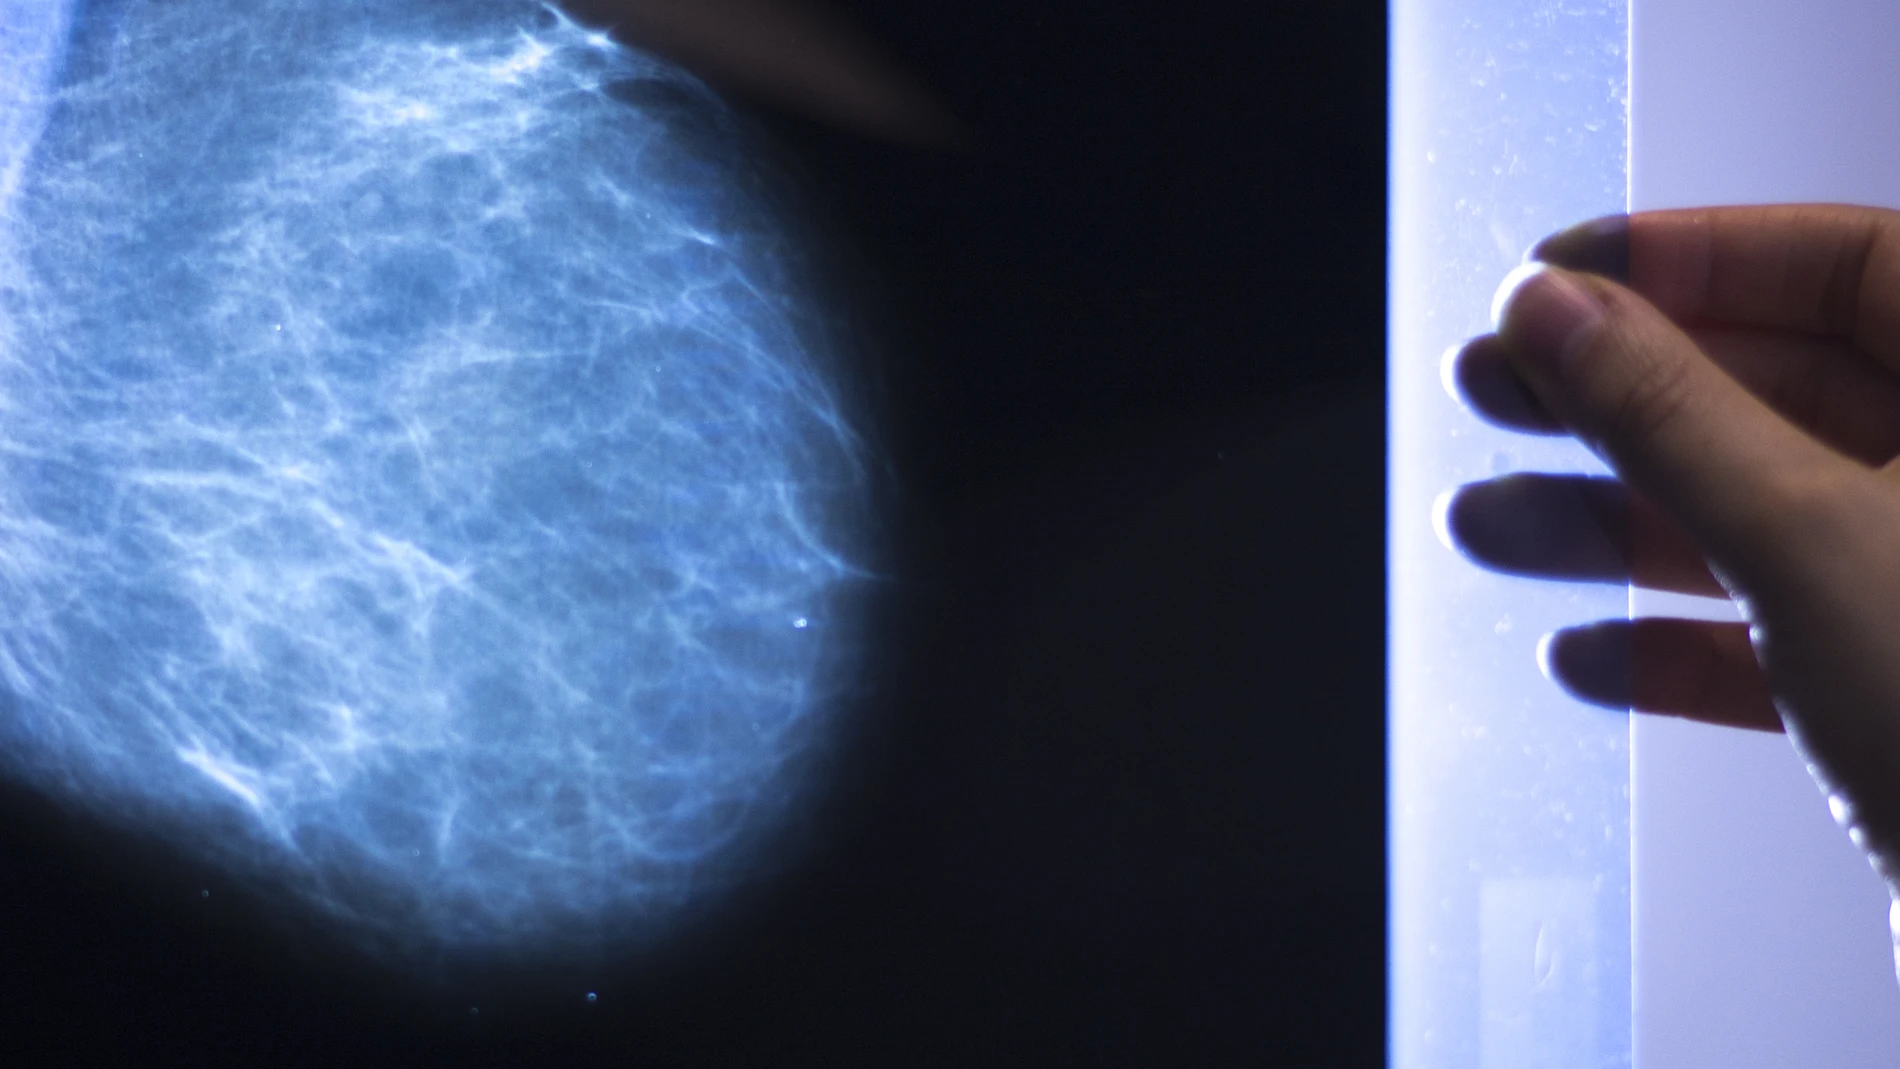

La crisis sanitaria que azota el mundo no se circunscribe solamente a la Covid-19 . Pacientes con otras patologías están sufriendo las consecuencias de la desviación de los recursos hospitalarios al tratamiento de la infección. Este problema es especialmente relevante en la atención al cáncer. Un análisis realizado por varias sociedades científicas relacionadas con el tratamiento oncológico, en base a datos recogidos desde marzo a junio de 2020, concluyó que, en España, 1 de cada 5 pacientes con cáncer no fue diagnosticado o fue diagnosticado tarde.

Los expertos insisten en que una detección a tiempo es clave para superar la enfermedad. En este contexto, resulta esencial contar con una asistencia médica completa y sin esperas. Así, la atención privada supone una opción interesante, junto con los seguros de vida, que se han ido adaptado a las necesidades surgidas de la pandemia. Las aseguradoras, por ejemplo, ofrecen productos cada vez más personalizados que puedan minimizar el impacto psicológico y económico del proceso oncológico. Es el caso de Life Care Mujer, de Banco Sabadell, que ofrece una cobertura completa para hacer frente a las necesidades económicas derivadas de la enfermedad.

Actualmente, el cáncer de mama es el tumor más diagnosticado en el mundo. Según la Sociedad Española de Oncología (SEOM), el año pasado se detectaron en nuestro país 32.958 casos, lo que lo convierte en el principal tumor diagnosticado en mujeres, seguido del cáncer colorrectal. La Asociación Española contra el Cáncer (AECC) estima que, entre gastos directos, ocultos y pérdida de ingresos por bajas, despidos y reducciones de horarios, el coste de este tumor puede ascender hasta los 42.000 euros. Cerca de 9.200 euros corresponderían a gastos directos como productos farmacéuticos o servicios médicos sanitarios. En concreto, el 96% de las pacientes ha gastado una media de 3.590 euros en gastos médicos como servicios de nutrición, pruebas y consultas en la sanidad privada, servicios de psicología o rehabilitación, entre otros.